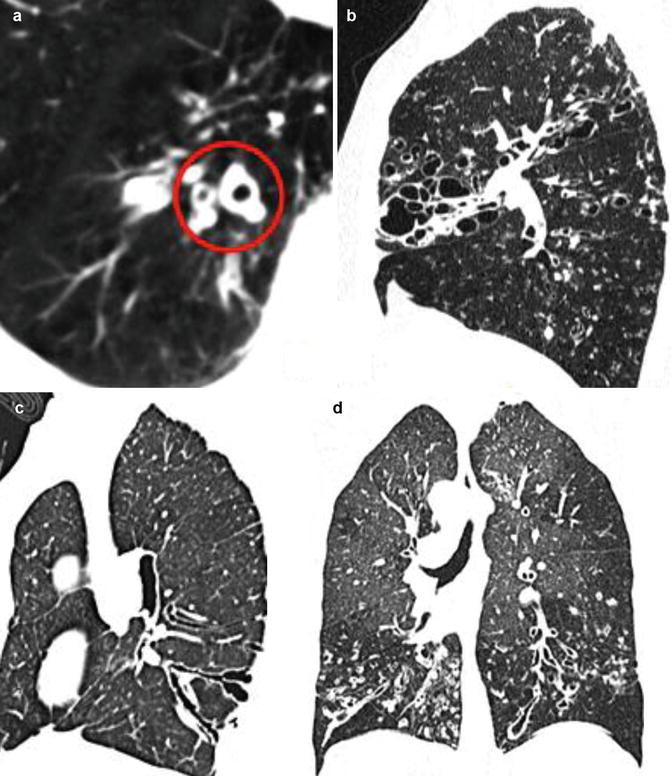

Fig. 16.

Thin-section CT findings in bronchiectasis. (a) The so-called signet ring sign (circle), a bronchus with an internal diameter greater than the diameter of the adjacent pulmonary artery. (b) Sagittal reconstruction shows a bronchiectatic bunch of grapes in the middle lobe. (c) Sagittal reconstruction shows lack of airway tapering >2 cm distal to point of bifurcation, bronchial wall thickening, and bronchi abutting the pleural surface. The wall thickness evaluation varies depending on slice thickness and window levels. (d) Coronal reconstruction shows lack of airway tapering and mosaic attenuation pattern

Fig. 17.

Computed tomography findings in acute exacerbation of bronchiectasis. (a) Axial scan shows ring clustered cystic spaces in the lower right lobe with air–fluid levels (demilunes). (b) Coronal reconstruction shows right upper lobe clustered ill-defined centrilobular nodules with a tree-in-bud configuration by mucus-impacted small airways (bronchiolitis). (c) Coronal reconstruction shows bilateral cystic exacerbated bronchiectasis with air–fluid levels. (d) Axial closeup scan shows cystic bronchiectasis with fungal overinfection/mycetoma (arrow)